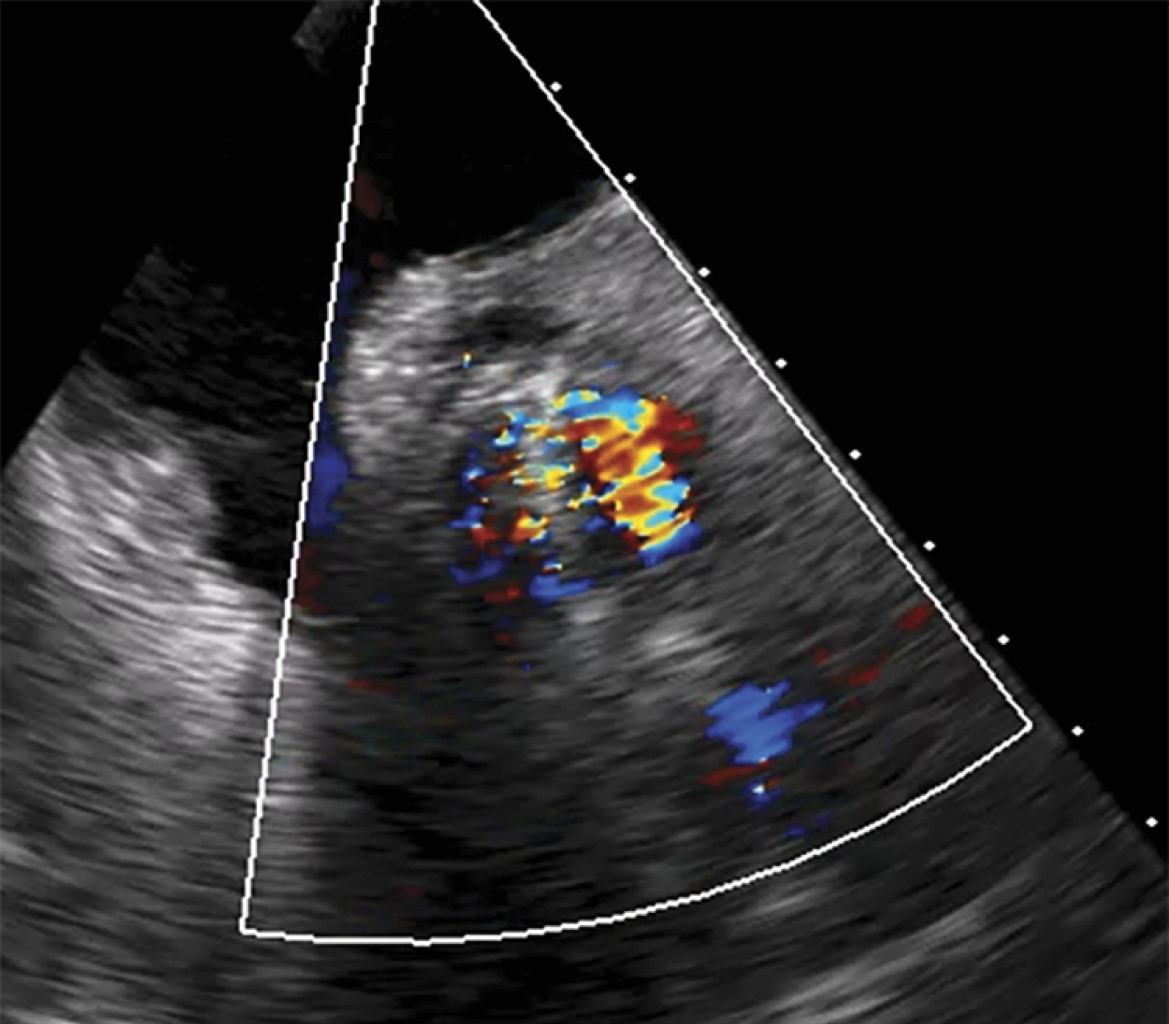

The patient was deemed a suitable candidate for valve replacement via cardiac surgery. However, to expedite treatment, a TAVI approach was employed. During the procedure, an Accurate Neo 2S 23 mm prosthesis (ACURATE neo2™, Boston Scientific, Marlborough, MA, USA), was implanted, but a residual valvular gradient of 25 mmHg was observed due to incomplete prosthesis deployment. To achieve optimal deployment, a post-implant dilatation of the aortic ring was performed, but a gradient of 20 mmHg persisted. Consequently, a second Accurate Neo 2S 23 mm prosthesis was implanted using the TAVI-in-TAVI technique. Unfortunately, during the second implantation, the first prosthetic valve migrated into the left ventricle (Figure 1).

Figure 1